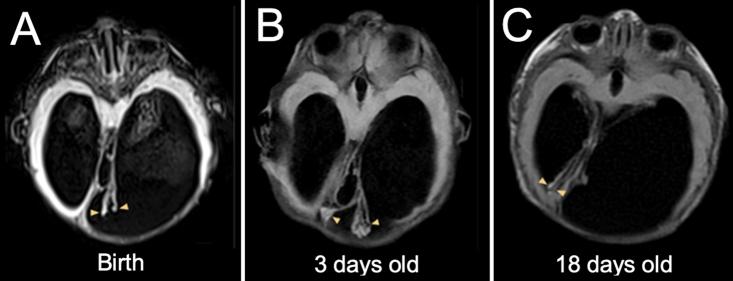

A female fetus was diagnosed with bilateral ventriculomegaly. Postnatally, the patient was diagnosed with hydrocephalus and macrocephaly secondary to aqueductal stenosis and underwent endoscopic third ventriculostomy with ChP cauterization. Intraoperatively, the septum pellucidum was incomplete, and the right-sided ChP glomus was contralaterally displaced and entangled with the left, with evidence of ischemic torsion and hemorrhage.

一名女胎被诊断为双侧脑室扩大。出生后,该患者被诊断为继发于导水管狭窄的脑积水和巨头畸形,并接受了内镜下第三脑室造瘘术及脉络丛烧灼术。术中发现透明隔不完整,右侧脉络丛球部向对侧移位并与左侧脉络丛缠绕,有缺血性扭转和出血迹象。